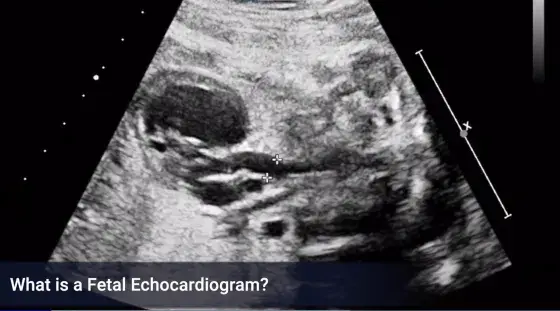

What is a fetal echocardiogram?

A fetal echocardiogram, also referred to as a “fetal echo,” is the most common form of ultrasound to evaluate the baby's heart in greater detail than typically performed during a routine ultrasound visit. The examination is performed by a specially trained ultrasound sonographer and the images are interpreted by either a pediatric cardiologist or a maternal-fetal medicine specialist (perinatologist). A fetal echo is usually performed after 18 weeks gestation and a full bladder is not required.